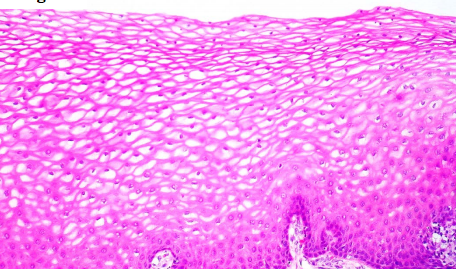

Stratified squamous, non-keratinized

Stratified Squamous Non-keratinized Epithelium

Stratified Squamous